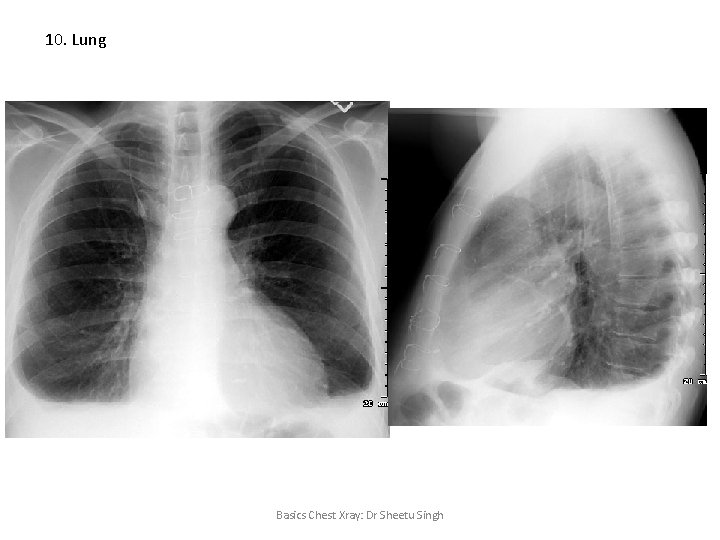

10. Lung Basics Chest Xray: Dr Sheetu Singh

10. Lung Emphysema • • Flattened diaphragm (terrace pattern) Tubular heart Increased rib spaces Increased retrosternal air spaces Basics Chest Xray: Dr Sheetu Singh